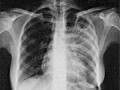

Знакомьтесь — туберкулезная палочка

24 марта — Всемирный день борьбы с туберкулезом. Эта проблема актуальна во всем мире, но особенно — в Украине, в том числе и в городе Ясиноватой. В 2008 г. рост заболеваемости туберкулезом в сравнении с 2007 г. составил 11,3%, в т.ч. тяжелыми деструктивными формами, удельный вес которых составил 57,1%, что говорит о поздней обращаемости! Несмотря на тяжелую эпидемическую ситуацию, в городе растет количество отказов от прививок БЦЖ и от диагностической реакции Манту, что называется: «пилим сук, на котором сидим».